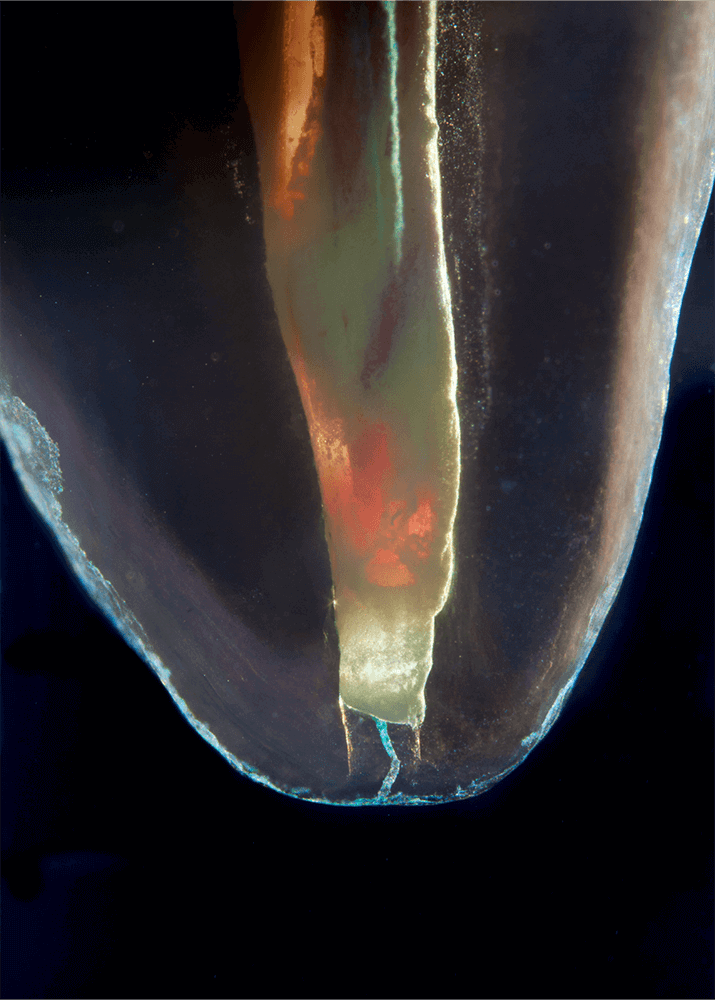

Das Verfahren, Zähne in durchsichtige Präparate zu überführen ist schon über 100 Jahre alt. Aber erst durch die Weiterentwicklung der alten Technik und die Kombination mit moderner Fotografie sowie der Entwicklung eines geeigneten Gefäßes zur Fotografie ist es meinem Vater Dr. Holm Reuver gelungen, einzigartige Bilder vom Inneren der Zähne aufzunehmen.

Die Bilder sind in verschiedenen Größen wählbar und auch als POPART-Variante erhältlich. Sie sind hervorragend geeignet für die Beratung von Patienten vor endodontischen Behandlungen, aber auch ein beliebter Eyecatcher im Wartezimmer. Außerdem haben die Bilder einen bedeutenden Stellenwert für die Erforschung der Pulpatopografie und für die Lehre im Bereich der Endodontie.

und die von ihm angefertigten Bilder, laden wir Sie ein, seine Begeisterung zwischen Wissenschaft und Kunst mit ihm zu teilen.